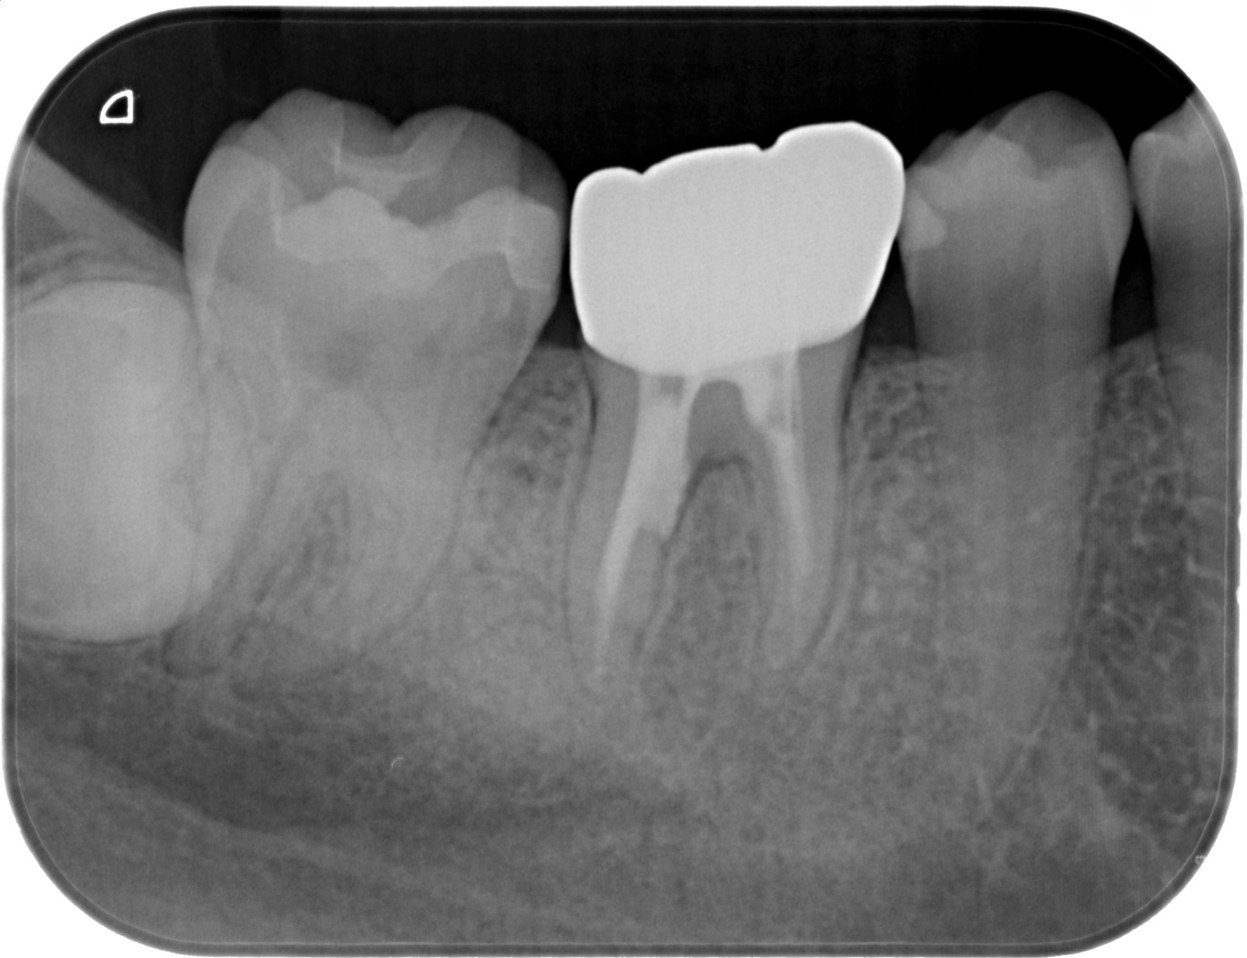

症例1:パーフォレーションリペア症例

(歯の中に大きな穴が空いてしまっているのを埋めて再生を促す治療)

歯に穴が空いていて骨に炎症がある状態 |

CTでも歯の周囲に骨がないのが分かる。 |

BEFORE |

AFTER |

人為的根穿孔を起こした部分に感染を起こしており、歯周ポケットが9㎜ありました。 ラバーダム防湿とマイクロスコープを使用して丁寧に治療を行いました。 殺菌性があり歯を補強することのできるMTAという根管充填材料を使用して、歯周ポケットは2㎜に改善しました。 |